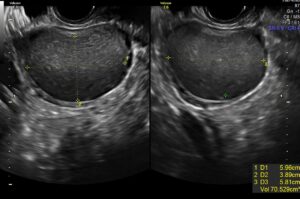

Como é um endometrioma

O endometrioma é um cisto que cresce no interior do ovário. A cápsula do endometrioma apresenta em sua superfície interna células da endometriose, que mensalmente sangram o para o interior do cisto, aumentando as suas dimensões.

Com o aumento das dimensões do cisto, surgem sintomas de dor pélvica, distensão abdominal, cólicas, dor na relação sexual e compressão dos folículos ovarianos, dificultando o seu desenvolvimento e aumentando as chances de infertilidade.